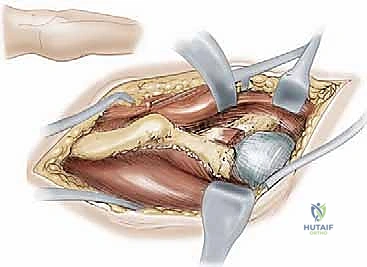

The Surgical Approach and Deep Dissection

We standardly employ the longitudinal anterior Smith-Petersen approach, which provides unparalleled direct access to the anterior pelvis. While a transverse "bikini" (ilioinguinal) incision offers a superior cosmetic result, it can severely restrict access to the deep anterior ischium, particularly in muscular or obese patients. The skin incision begins slightly proximal and lateral to the ASIS, extending distally along the interval between the tensor fasciae latae (TFL) and the sartorius.

During the superficial dissection, meticulous identification and protection of the lateral femoral cutaneous nerve (LFCN) are paramount. The fascia over the TFL is incised, and the interval between the TFL and the sartorius/rectus femoris is developed. The ASIS is often managed via a thin wafer osteotomy, leaving the sartorius and inguinal ligament attached, which facilitates later repair and prevents avulsion. Deep dissection involves elevating the iliacus muscle subperiosteally from the inner table of the ilium, exposing the pelvic brim, the quadrilateral plate, and extending posteriorly toward the greater sciatic notch.

Simultaneously, the outer table of the ilium is exposed by elevating the abductor musculature (gluteus medius and minimus) just enough to visualize the supra-acetabular region and the capsule. The rectus femoris origin at the AIIS is identified; the direct head is typically preserved, while the reflected head may be released to expose the superior joint capsule. Blunt retractors (such as a Hohmann or a specialized Ganz retractor) are carefully placed over the pelvic brim and into the obturator foramen to protect the neurovascular bundle during the subsequent osteotomies.

Reorientation and Definitive Fixation

Once liberated, the acetabular fragment is highly mobile. Using the Schanz pin as a joystick, the acetabulum is reoriented to achieve the preoperatively templated coverage. Typically, this involves anterior and lateral rotation (extension and abduction of the fragment) and medialization of the hip center. The fragment is temporarily held with long Kirschner wires.